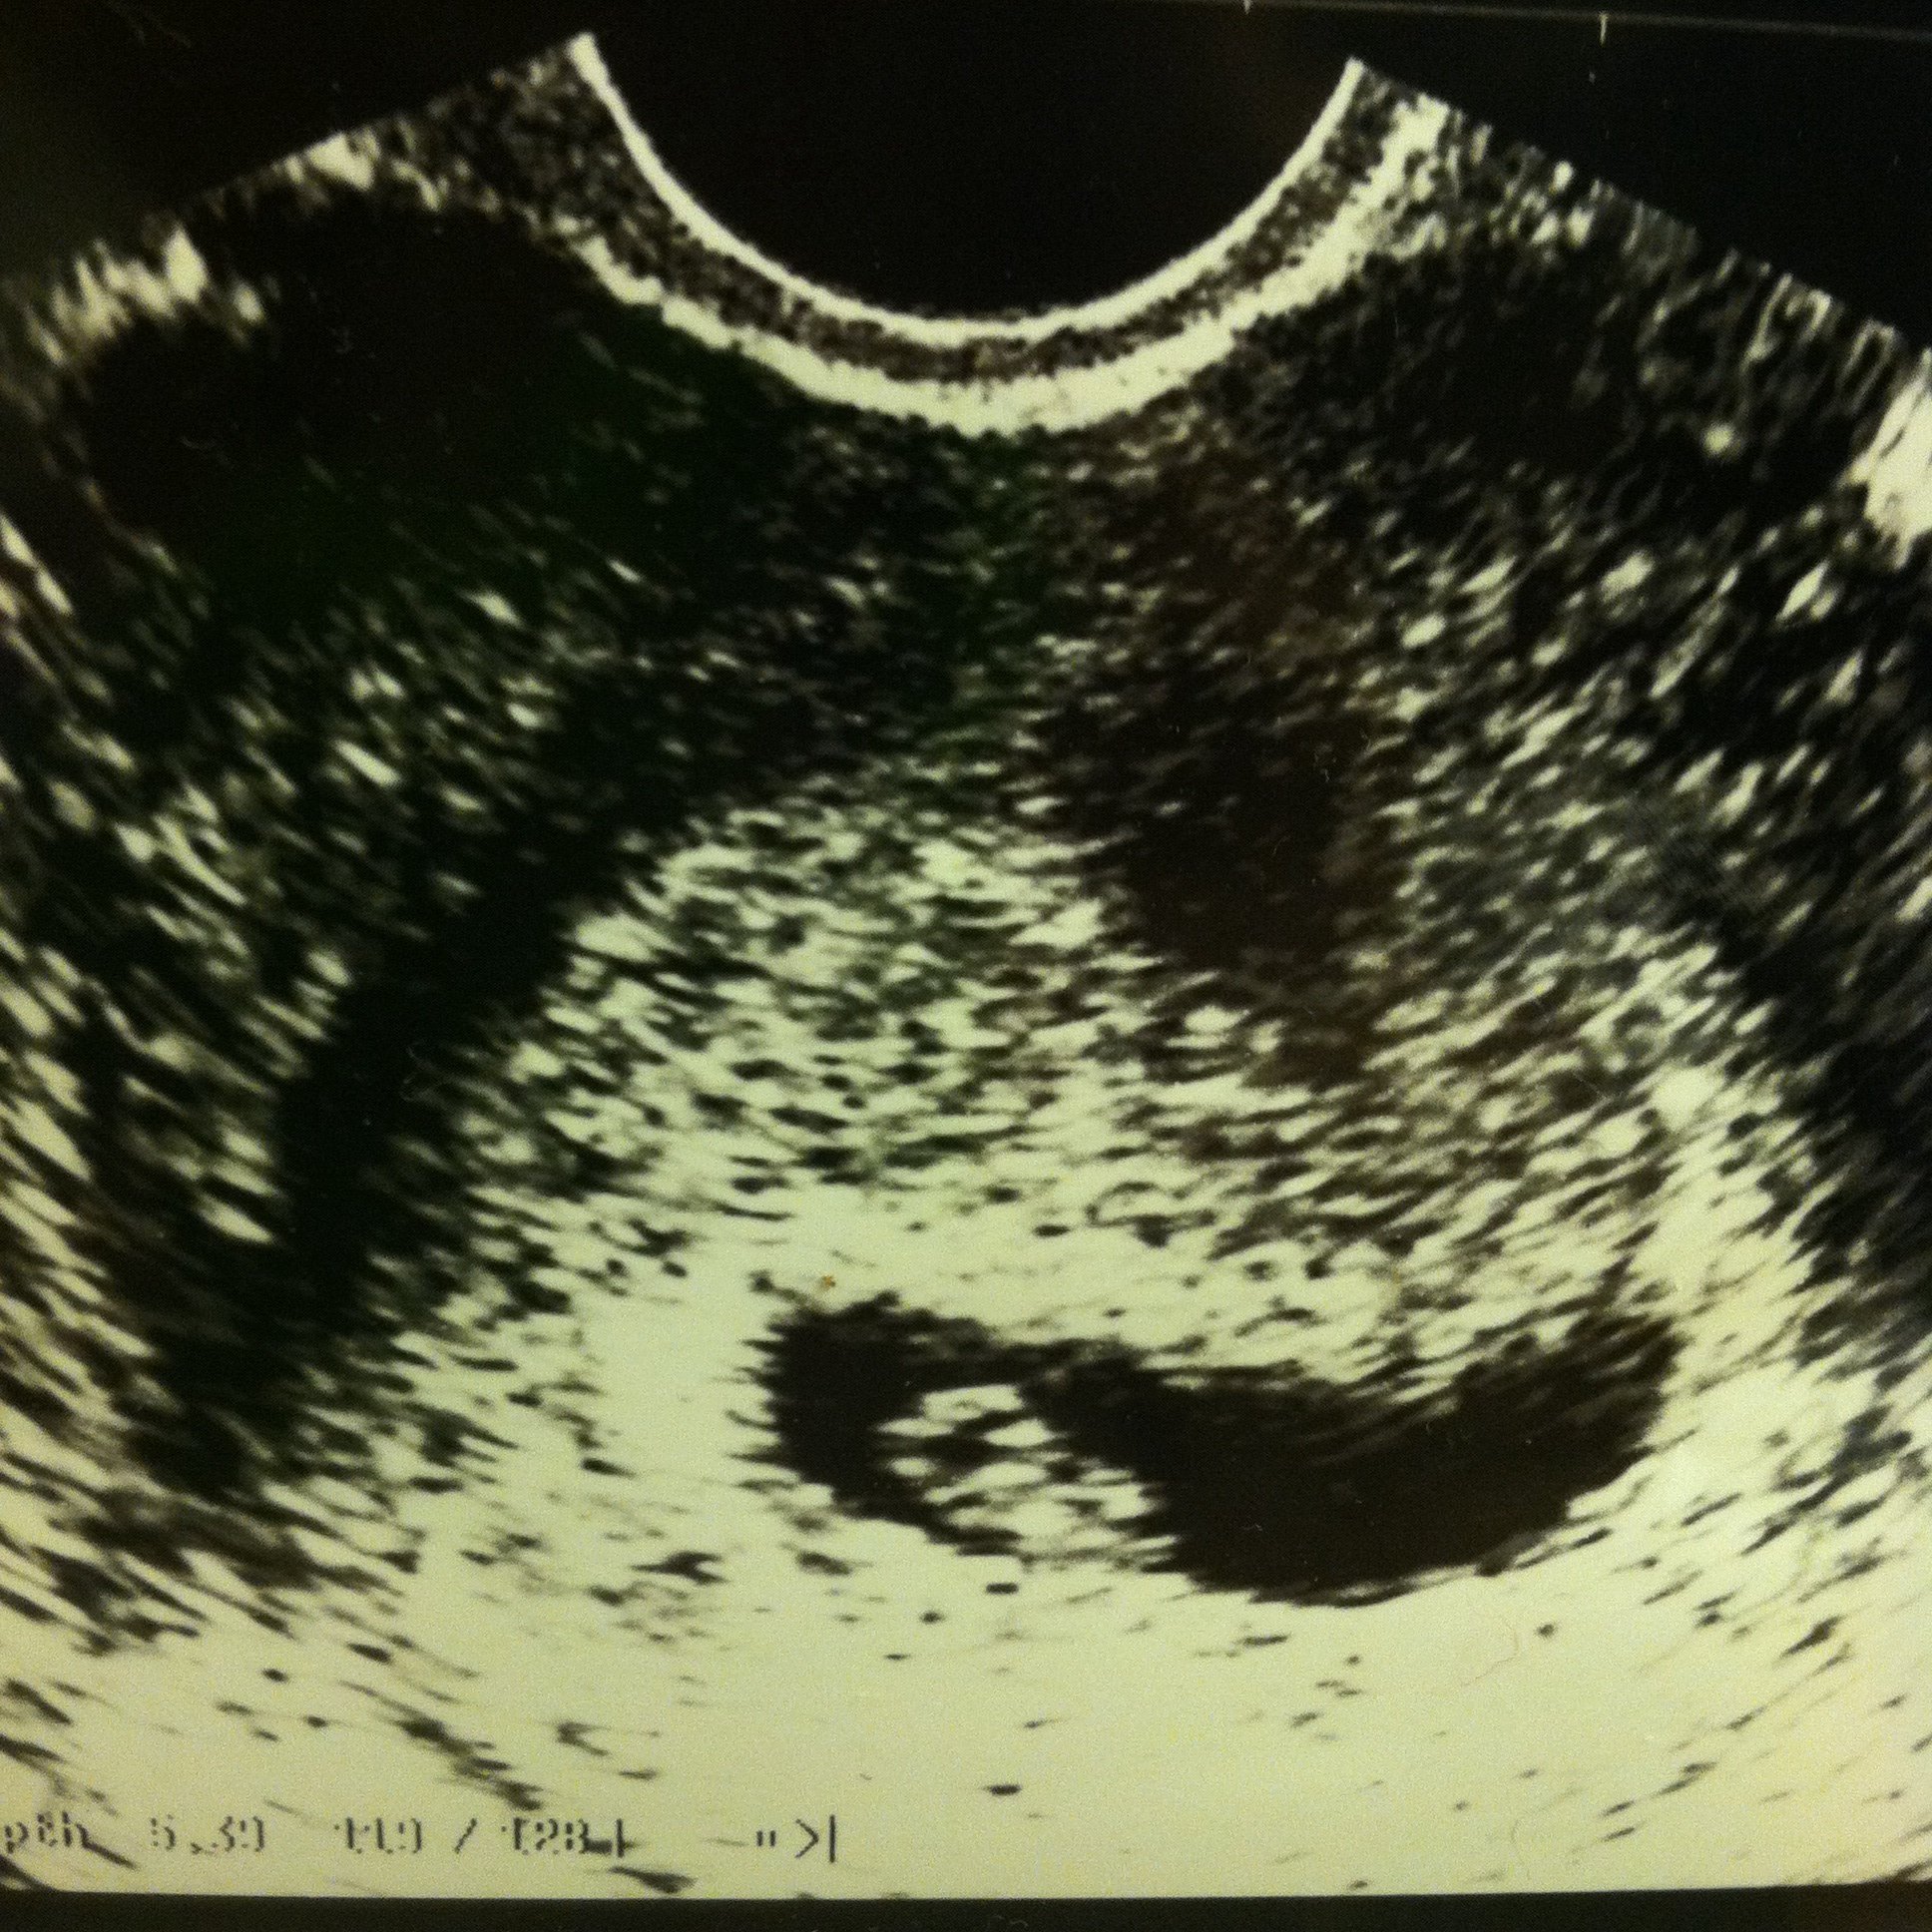

Just curious if anyone has any experience with this. Going in for a 5th ultrasound next week because they first few times there was no visible bladder or stomach bubble. The last time they did one nothing was visible, they had me wait 45 mins and we did another and the bladder was visible, though very small, but still no stomach. Just wondering if anyone else has gone through this..